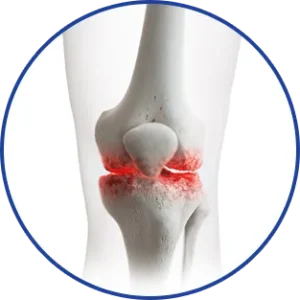

ARTICULACIONES rígidas

Movilidad reducida

Dolores constantes

REDUCCIÓN INMEDIATA DEL DOLOR: Sensación refrescante que adormece el dolor al contacto. Gel para dolor articular

ACCIÓN DIRIGIDA: Reduce la inflamación y la rigidez exactamente donde lo necesitas.

- Reducción de la rigidez de las articulaciones y los músculos